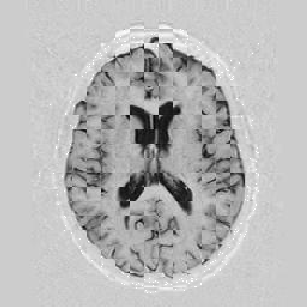

Lastly, Figure [*] shows 10 iterations at level 2, 6 iterations at level 1, and 6 at level 0.

Figure: Multi-scale NRR. From left to right, top then bottom: before NRR; after 10 iterations of NRR at level 2; after another 6 iterations of NRR at level 1; after 6 more iterations at level 0.